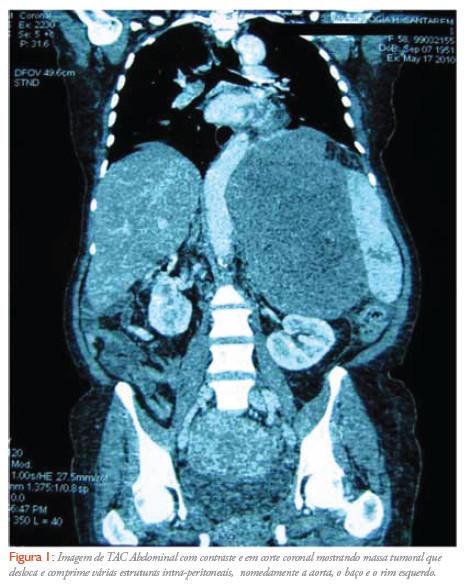

Mulher de 58 anos, caucasiana, viúva, natural e residente em santarém, com antecedentes de HTA, diabetes mellitus tipo II, AVC isquémico sequelar e anemia microcítica. Recorre ao serviço de Urgência do hospital distrital de santarém (HDS), por epigastralgias e astenia com 4 meses de evolução e agravamento da frequência e intensidade na última semana, perda de peso de aproximadamente 15 kg nos últimos dois meses e saciedade precoce. Ao exame objectivo apresentava-se vigil, desorientada no tempo, pouco colaborante, idade aparente superior à real, corada, hidratada, emagrecida. À inspecção abdominal detectou-se proeminência na região epigástrica, palpando-se massa de consistência dura, não dolorosa, que se estendia até 7 cm abaixo da apófise xifoideia. De referir ainda ligeira diminuição da força muscular à direita, sequela do AVC. A doente ficou internada no serviço de medicina por epigastralgias de etiologia a esclarecer. Realizou-se TAC Toraco-Abdomino-pélvica que revelou volumosa massa tumoral atingindo o epigastro, o hipocôdrio e o flanco esquerdos mede aproximadamente 20 cm de maior eixo no plano axial, tem limites relativamente nítidos não se observam adenopatias . A nível hepático não se evidenciam lesões focais (Figura 1). O caso clínico foi discutido em consulta multidisciplinar de decisão terapêutica onde foi considerada a indicação para ressecção cirúrgica urgente. A doente foi submetida a tumorectomia, pancreatectomia caudal e esplenectomia por aderência da massa tumoral ao baço e pâncreas. Tanto o procedimento cirúrgico como o pós-operatório decorreu sem intercorrências com alta médica no 12º dia após a intervenção. O resultado anatomo-patológico foi: peça de tumorectomia que pesa 3800g e mede 25x25x15cm. Macroscópicamente o tumor estava quase totalmente coberto por peritoneu, e a superfície de secção era acinzentada, sólida e mole, tendo uma área de necrose central que ocupa 60% da massa tumoral.Microscópicamente o tumor mostrava focalmente padrão fusocelular e estoriforme, predominando, no entanto, as áreas desorganizadas constituídas por células marcadamente pleomórficas (Figura 2). Imunohistoquimicamente identificou-se positividade intensa com Vimentina, e focal e escassa com Actina de músculo liso e CD34, sendo o CD117 (C-Kit) e os restante marcadores de diferenciação epitelial, miogénica, lipogénica e neural negativos. Isolam-se 8 gânglios com diâmetros entre 0,1 cm e 0,7 cm. Conclusão: sarcoma pleomórfico indiferenciado de alto grau (histiocitoma fibroso maligno). Gânglios linfáticos sem metástases. O tumor rasa a margem cirúrgica. Baço e pâncreas aderentes ao peritoneu, sem infiltração tumoral. Na reavaliação em consulta multidisciplinar, foi considerado não haver indicação para tratamento adjuvante com quimio ou radioterapia, apesar do elevado potencial de recaída da lesão, ficando a doente em vigilância na consulta de Cirurgia do HDS.